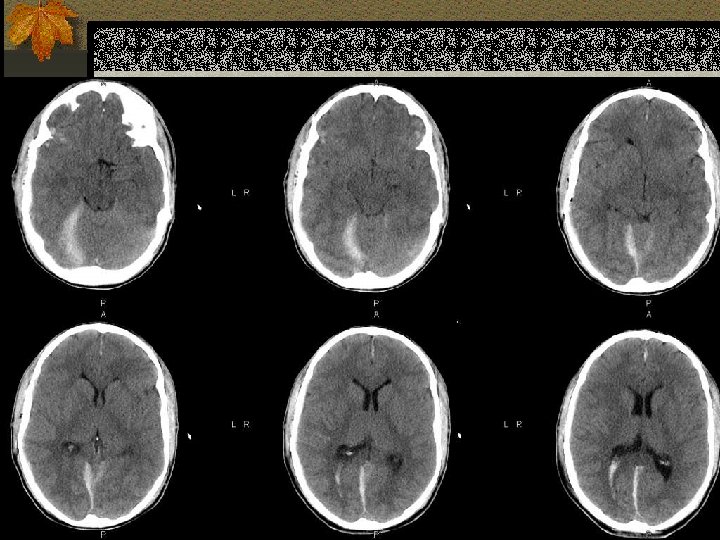

SUBDURAL HEMATOMA n Timbul antara dura dan arachnoid n Dapat melewati sutura n Timbul akibat disrupsi bridging cortical veins n Bentuk konkaf n Hipodens(hiperakut, kronis), isodens(subakut), hiperdens(akut)

W=33 L=41

PENANGANAN SDH n SDH akut dengan ketebalan > 10 mm atau pergeseran midline > 5 mm harus dievakuasi n Pasien yang koma dengan penurunan GCS >2 poin dengan SDH harus menjalani operasi evakuasi